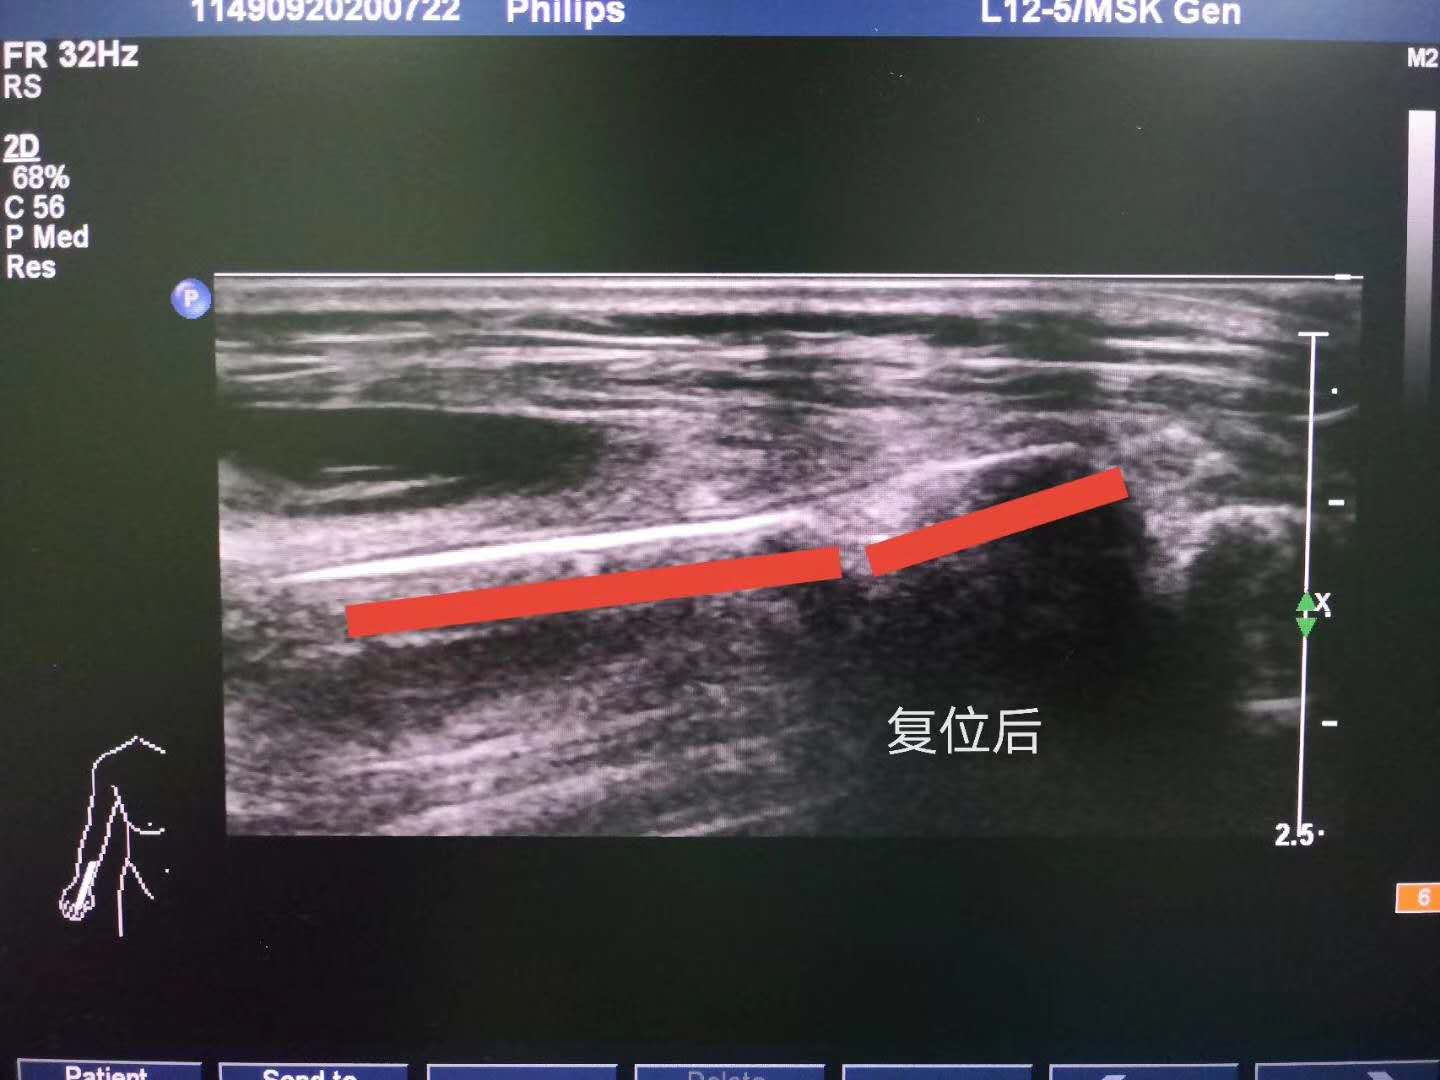

郑州院区手法正骨科副主任李晓峰听闻谭女士的情况,当机立断选择在肌骨超声引导下进行复位。因为谭女士处于孕期,李晓峰副主任非常慎重,在冯平医生和功能检查科张浩良医生的配合下精准定位,以高超的手法正骨技术,成功使骨折处复位,帮助谭女士解除了痛苦。

在肌骨超声引导下进行复位,既不用开刀手术,还免受了X线辐射,针对怀孕或有特殊情况患者很适用。李晓峰副主任的决定保护了一个小生命。患者家属说:“幸亏省骨科医院有这样的技术,才能这么顺利!感谢手法正骨科,才让这场意外只是虚惊一场!”